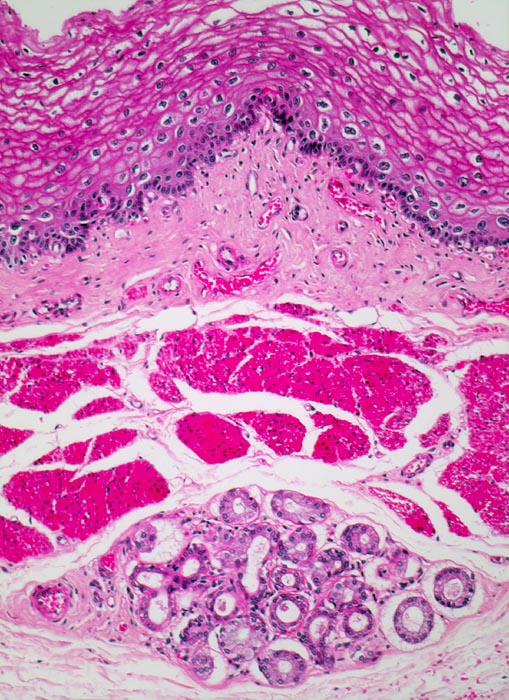

PathoPic – image database / PathoPic ID 4315 - normaler Ösophagus

normaler Ösophagus

Oesophagus

Auf das Plattenepithel folgt das bindegewebige subepitheliale Stroma und die glattmuskuläre Lamina muscularis mucosae. In der Submukosa befinden sich seröse Schleimdrüsen.

Histologie

100